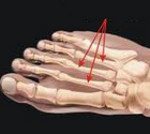

При болезни Дейчлендера изменения возникают в средней (диафизарной) части плюсневых костей. Патологическая перестройка костной ткани в данном случае обусловлена изменившимися механическими и статико-динамическими факторами. В процесс чаще всего вовлекается II плюсневая кость, реже - III, еще реже - IV и V. Подобное распределение обусловлено особенностями нагрузки на стопу при стоянии и ходьбе, поскольку в таких случаях больше «нагружаются» внутренние и средние отделы стопы. I плюсневая кость не поражается никогда. Вероятно, это связано с ее более высокой плотностью и прочностью.

При болезни Дейчлендера в области диафиза пораженной плюсневой кости (иногда - ближе к головке, иногда - к основанию, в зависимости от локализации наиболее функционально перегруженного участка) выявляется изменение структурного рисунка. Определяется косая или поперечная полоса просветления (зона просветления Лоозера) - область перестройки кости. Выглядит так, как будто плюсневая кость разделена да два фрагмента. Однако, в отличие от рентгенологической картины при переломе, смещения в данном случае не наблюдается.

В последующем вокруг пораженного отдела кости возникают периостальные разрастания. Вначале они тонкие и нежные, затем - плотные, похожие на веретенообразную костную мозоль. Позже зона просветления исчезает, наступает склерозирование.

С течением времени периостальные наслоения рассасываются. При этом кость навсегда остается утолщенной и уплотненной. Определяющими признаками являются отсутствие острой травмы, типичная локализация повреждения, а также наличие зоны перестройки при отсутствии смещения фрагментов и сохранении правильной формы кости.